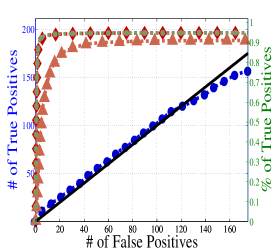

To understand the performance of this standard method, we present a small preview of our simulation study discussed later in Section 4. Briefly, we assume that each subject graph in group follows a small-world structure on nodes; in group , there are in addition 150 differential edges, meaning that and for all differential edges, . We generate data according to this model with time points and subjects in each group. Figure 1 illustrates the results of this standard approach as well as our new procedure, , which we will introduce later in Section 3. Part (a) gives ROC curves for the number of false positives verses true positives as each sequential test is rejected; parts (b) and (c) give the adjacency confusion matrix illustrating where the true and false positive as well as false negative edges are detected in the graph structure.

Our motivating simulation shows that the standard approach performs terribly in terms of both error control and statistical power. While the magnitude of the poor performance of this approach may seem astonishing, the poor performance should come as no surprise: The inferential procedure (e.g. test statistics) of the standard approach assume a one-level model that would be appropriate when the subject graphs are fixed and known or directly observed quantities. When these subject networks are unobserved, however, and must be estimated from finite data, these one-level test statistics are incorrect for our two-level problem. Specifically for two-level problems, the variance of parameters estimated by incorrectly assuming a one-level models is underestimated. For our problem, the extra source of variability arises from the graph selection procedure; we discuss challenges associated with this subsequently in Section 2.2. Incorrect variance estimates, however, are not the only problem with the standard approach: A more subtle problem arises from the fact that the proclivities of graph selection procedures for the Gaussian graphical model lead to biased estimates of the edge proportions, . As discussed in Section 2.3 and seen in Fig 1, graph selection false positives and false negatives do not occur at random throughout the network structure, leading to biased group level estimates.

Hence, the first term represents variability across subjects in group and the second term represents the variability associated with the selection procedure within subject , a quantity that we assume to be constant across subjects in each group . Consider now what happens if our true model follows this two-level Beta-Binomial model, but as with the standard approach, we use a one-level Binomial model and associated two-sample test statistic. The variance is thus underestimated and the test statistic is overoptimistic. Then, when inference is conducted for the population mean , using the incorrect Binomial model leads to inflated Type I error rates; this behavior has been well-documented (Weil, 1970; Liang and Hanfelt, 1994). Hence, failure to use the correct two-level model which accounts for the two levels of network variability partially explains the high error rates of the standard procedure observed in Figure 1.

In Figure 4 and Table 1, we present our main simulation results comparing to the two variations of our method and the standard approach for three network structures and Case I and II type differential edges. First for Figure 4, we report results in terms of operating characteristics averaged across 50 replicates with the number of true positives (y-axis) plotted against the number of false positives (x-axis) for each test statistic, rejected sequentially from largest to smallest in absolute magnitude. Overall, all of our methods and particularly yield substantial improvements over the standard approach in all scenarios.

Notice that both and =(RS,RP) share similar orderings of test statistics, and consequently similar ROC curves. Overall, methods that include random penalization yield major improvements in statistical power over those that do not. This indicates that the second popPSI challenge outlined in Section 2.3 is a significant contributor to the poor performance of the standard method. Recall our discussion of how graph selection errors at the subject stage occur non-randomly and hence bias our group-level estimates of . Our results empirically demonstrate that random penalization dramatically improves these biases, leading to less bias in our test statistics and hence improvements in both Type I and Type II error rates. Furthermore, in Case II scenarios where selection errors are moderate, the performance gap between any method containing over reduces compared to Case I scenarios where selection errors are more severe. Thus, the benefits of random penalization are greater when selection errors are more abundant. Confusion adjacency matrices illustrating the location of inferential errors for our methods shown in the supplemental materials also indicate that random penalization improves graph selection in cases where there are larger correlations between differential edges and common edges. Similar results hold for our high-dimensional study presented in the supplemental material.

Table 1, which accompanies Figure 4, gives the empirical true positive and false discovery rates (FDR) averaged over 50 simulation replicates when the Benjamini-Yekutieli (Benjamini and Yekutieli, 2001) procedure controlling the FDR at 10% is used to determine the number of tests to reject. First, notice that the observed false discovery proportion (FDP) of our procedure is not 10% on average, indicating that our method does not fully control the FDR. This occurs because we specifically simulate difficult and realistic fMRI scenarios with graph structures that severely violate irrepresentable-type conditions. In situations (not shown) where irrepresentable-type conditions are met that ensure graph selection consistency, our procedure as well as the standard method correctly control the FDR. As discussed in Section 2.3, in situations where graph selection errors occur with high probability, it is likely impossible to provably control the FDR, consistent with our empirical results. Yet even though does not fully control the FDR, our error rates are dramatically improved over the standard approach and other variations of our procedure.

Also in Table 1, observe that (RS,RP), which had similarly ordered test statistics to , has dramatically worse Type I error rates that do not come close to controlling the FDR. While (RS,RE) also does not control the FDR, the error rates are much improved over (RS,RP). These results demonstrate that using two-level models with the correct random effects test statistics are crucial to Type I error control. Recall from Section 2.2, that using the one-level Binomial model leads to an under-estimation of the variance term which in turn inflates test statistics and leads to an increase in false positives. Note also that the estimated FDP of is still a major improvement over that of (RS,RE). This occurs as the problem of graph selection errors induces both Type I and Type II errors. Hence, these results demonstrate the necessity of all three of our ingredients. Finally, observe that our error rates in Case II scenarios are better than those for Case I scenarios, again indicating that differential edges that are highly correlated with non-edges and common edges pose particular challenges for our popPSI problem. These results are also corroborated in our high-dimensional study presented in the supplemental materials.

Lastly, in Figure 5, we study the effect of letting the network structure vary across subjects by decreasing the differential group edge probability, . Our method continues to perform well for . However, when the differential edge probability drops further to , we see that both and the standard approach have greatly reduced statistical power, as one would expect. Despite this, continues to outperform the standard approach.